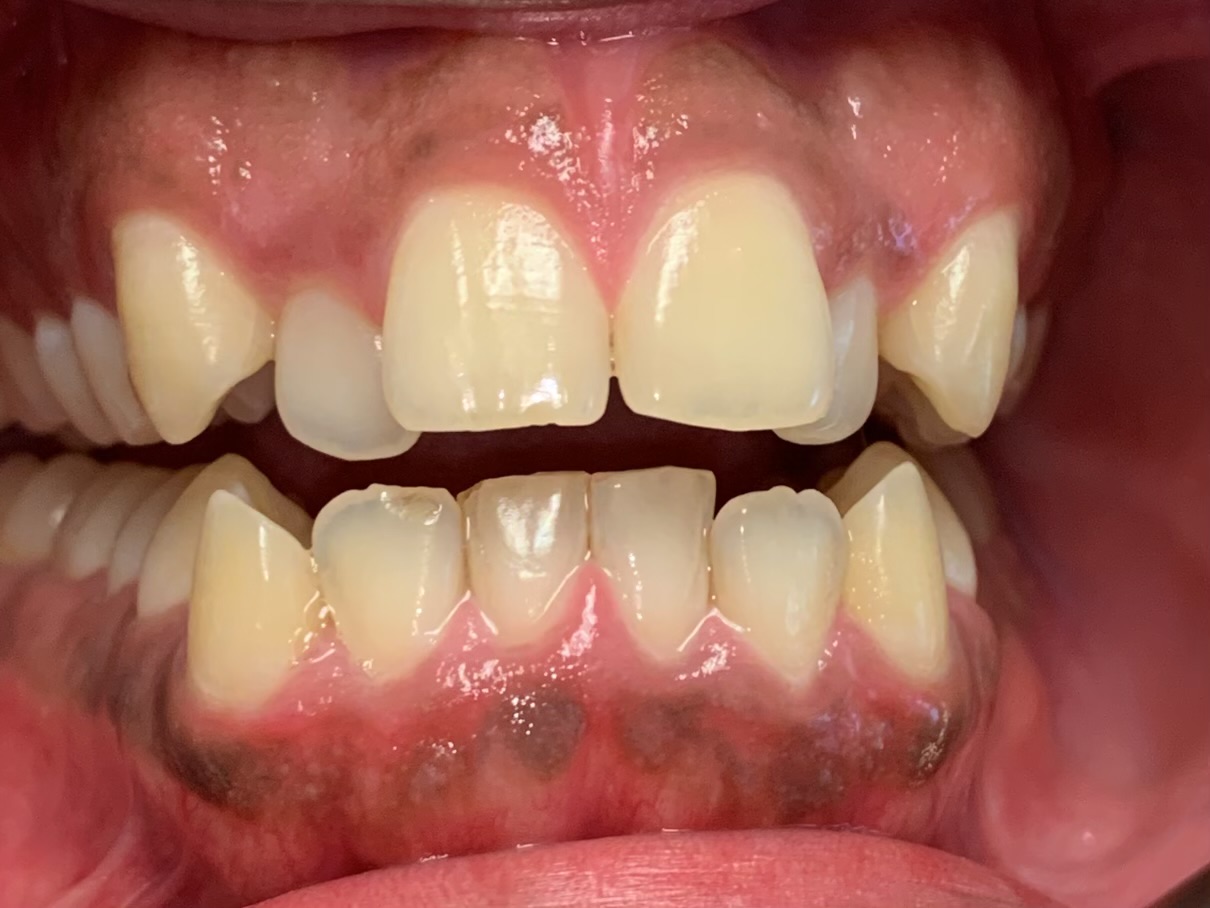

At Gramercy Smiles we are dedicated to creating lasting smiles through comprehensive care using the latest technology. We proudly offer personalized, patient-driven care focused on the health, beauty, and functionality of your teeth. Please browse our smile gallery below and contact us to schedule a smile consultation today.